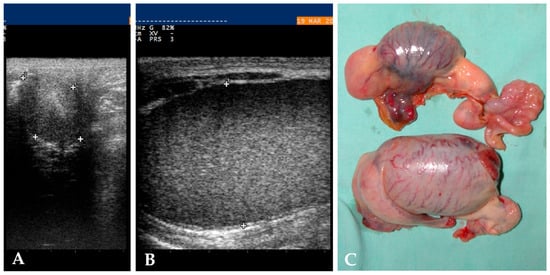

Cryptorchidism in Equid: A Retrospective Study on Diagnostic Approach, Anaesthesia Management, Surgical Treatment and Outcomes

Over the years, various diagnostic and surgical techniques have been developed to recognise and treat cryptorchidism in equid. This study retrospectively analysed cases of cryptorchidism referred to two centres between 2012 and 2025. Clinical data collected included species, breed, age, gender, location of [...] Read more.

Over the years, various diagnostic and surgical techniques have been developed to recognise and treat cryptorchidism in equid. This study retrospectively analysed cases of cryptorchidism referred to two centres between 2012 and 2025. Clinical data collected included species, breed, age, gender, location of retained testis, diagnostic approach, anaesthesia plan and surgical treatment, perioperative medical treatment, intra-operative complications and outcomes. A total of 37 clinical cases were included, 1/37 was a donkey and 1/37 was an intersex female. Most of the horses were three years old and belonged to western riding horse breeds. Ultrasound examination correctly identified the location of the retained testis in 87% of cases. The anaesthesia plan includes a local anaesthesia block, mainly a local injection for the infiltration of the retained testis. The laparoscopic standing flank technique was the main approach, performed in 82% of cases. Complications were encountered in 9% of cases, and the median discharge time was 2 days. In our study, Quarter Horse-type horses were overrepresented, and three horses were sons of the same Quarter Horse stallion, suggesting a genetic component in aetiology. The use of ultrasound might confirm cryptorchidism in both abdominal and inguinal locations. Standing flank laparoscopy was the most frequently chosen procedure, over recumbent laparoscopy and inguinal open orchiectomy. The outcome reported a low rate of intra-operative complications. Full article

Show Figures

Figure 1